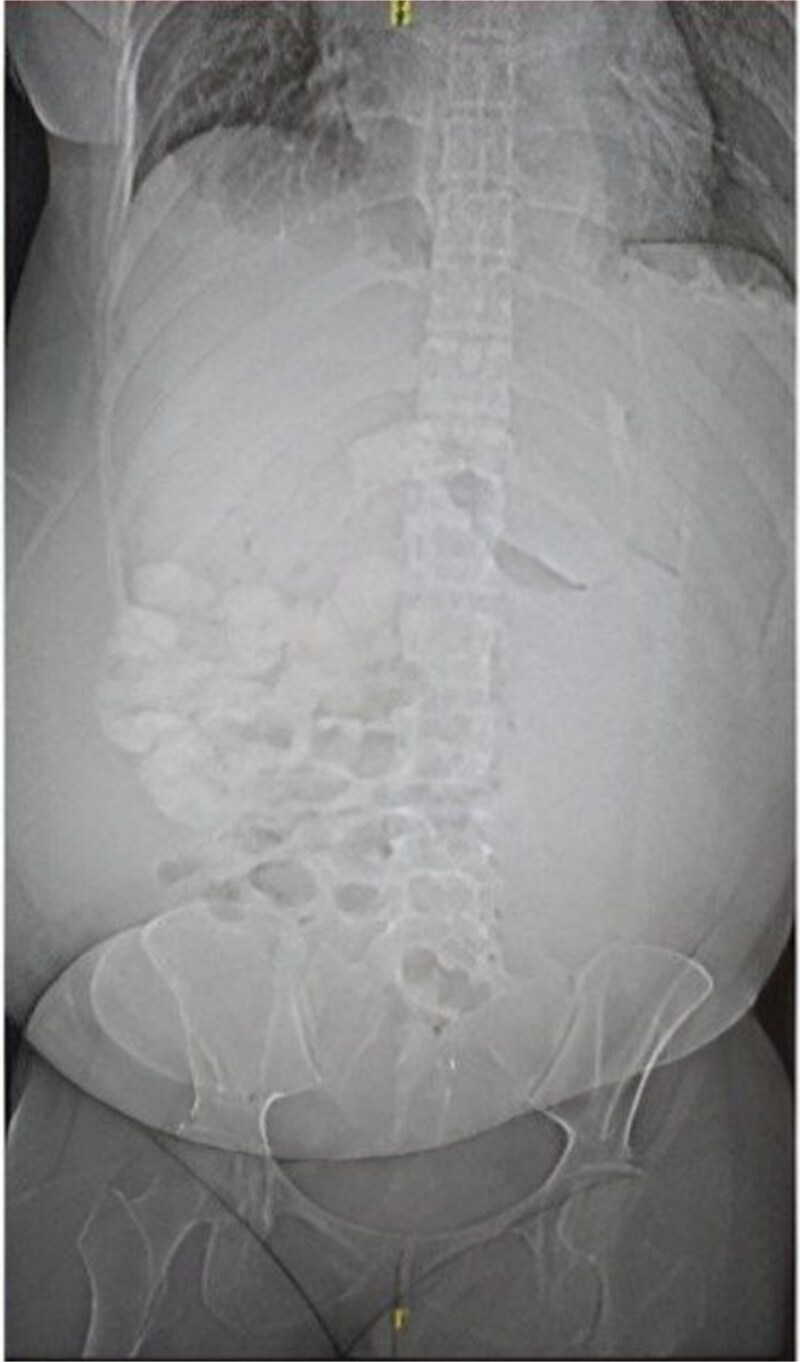

灾难性抗磷脂综合征(CAPS)是一种罕见的严重形式的APS,其特征是多器官血栓形成和细胞因子风暴。我们报告了一例复杂的病例,一名28岁的女性,她的COVID-19检测呈阳性,有深静脉血栓形成、肺栓塞和系统性红斑狼疮病史,并伴有潜在的APC,并发多器官CAPS。计算机断层扫描(CT)显示广泛的肺栓塞和右/左心室比值(RV/LV)升高。腹部及骨盆CT示胃炎、腹水及腹水、积液及双侧少量胸腔积液。尿液分析显示低水平的白蛋白,尿蛋白4+ g和高脂血症。实验室检查显示患者已发展为恶化的非少尿急性肾损伤和肾活检显示坏死性坏死。这是一个复杂的病例,有助于了解CAPS,并突出了其诊断和管理的挑战。

Catastrophic Antiphospholipid Syndrome (CAPS) is a rare serious form of APS characterized by thrombosis in multiple organs and a cytokine storm. We report a complex case of a 28-year-old female that tested positive for COVID-19 with a medical history of deep vein thrombosis, pulmonary embolus and systemic lupus erythematosus, with underlying APC, complicating her case of CAPS in multiple organs. Computed Tomography (CT) PE reveled extensive pulmonary emboli and an elevated right/left ventricular ratio (RV/LV). CT of the abdomen and pelvis showed gastritis, ascites and anasarca, fluid accumulation and small bilateral pleural effusions. Urinalysis showed low levels of albumin, urine protein 4+ g, and hyperlipidemia. Laboratory test indicated that the patient has developed a worsening non oliguric acute kidney injury and renal biopsy revealed necrotizing. This is a complex case that contributes to the understanding of CAPS and highlights the challenges of its diagnosis and management.